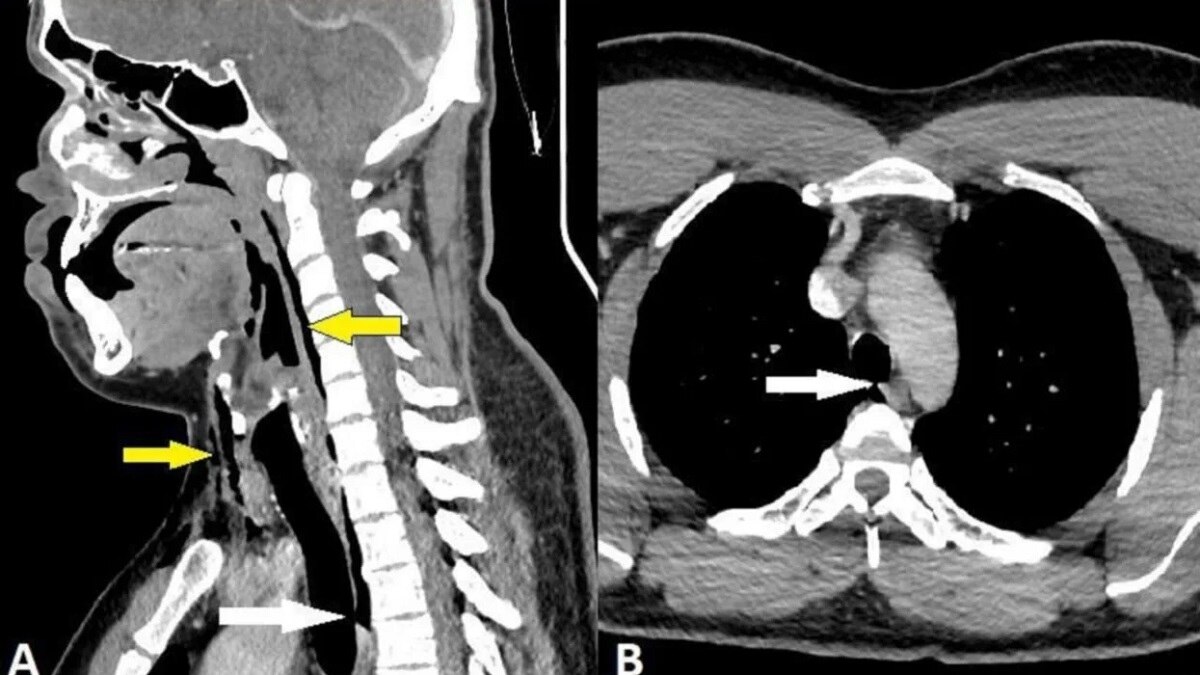

एक्स-रे कराने के बाद पता चला कि उस आदमी को सर्जिकल एमफीसेमा नामक एक बीमारी थी, जहां हवा किसी के शरीर के सबसे गहरे टिशूज के नीचे फंस सकती है.छींक रोकने पर हवा उस आदमी की गर्दन में कशेरुकाओं के साथ-साथ उसकी छाती और फेफड़ों के बीच की जगह में फंस गई थी.अंततः, डॉक्टरों ने यह समझा उस उसको सर्जरी की जरूरत नहीं है.